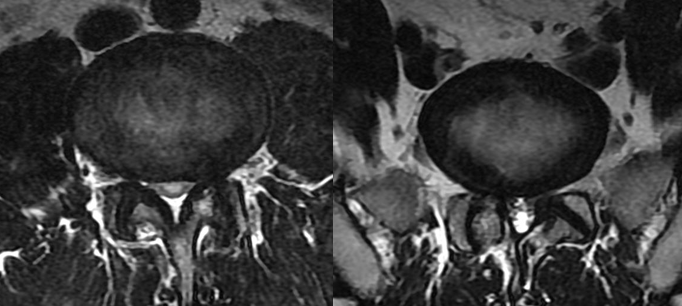

椎管狭窄  (先天性、继发性)

定义:椎管(或侧隐窝)变小,引起鞘膜囊及其内容物受压称为椎管狭窄。可合并椎间孔狭窄。

分类

• 先天性椎管狭窄

• 继发性椎管狭窄:

•   1)黄韧带肥厚

•   2)后纵韧带钙化及骨化

•   3)椎小关节退行性变

• 侧隐窝狭窄

• 椎间孔狭窄

MRI表现

颈腰段椎管前后径:相对狭窄- 12~15mm绝对狭窄-小于10mm。